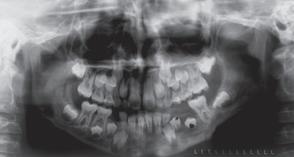

Formål: At evaluere molarernes intramaksillære forskydninger og forandringen i molarrelationerne efter brug af en »lip bumper« i kombination med et bidplateau.

Materiale og metode: Materialet omfattede studiemodeller taget før og efter behandling af 40 konsekutivt behandlede patienter i blandingstandsættet. De sagittale og transversale tandforskydninger blev evalueret ved hjælp af en tredimensional digitaliseringsenhed. De palatale rugae blev anvendt indirekte som stabil reference. Tandbevægelserne blev udtrykt som translation mesiodistalt og faciolingualt, som rotation omkring den lange akse og som tipning mesiodistalt. Ændringer i molarrelationen blev målt til nærmeste millimeter parallelt med okklusalplanet.

Resultater: Tandbevægelserne var overvejende distal rotation (gennemsnit 9°, varierende fra 6,5° til 26°) og distal tipning (gennemsnit 5°, varierende fra 5,8° til 18°). Den distale translation var beskeden (gennemsnit 0,3 mm, SD 1,6 mm), hvorimod der var en større breddeøgning i form af en facial translation (gennemsnit 1,6 mm, SD 1,5 mm). Med undtagelse af fire kvadranter forbedredes molarrelationerne i alle kvadranter, og neutral okklusion opnåedes i 65 ud af 80 kvadranter.

Konklusion: Den tidlige behandling med »lip bumper« og bidplateau kan anbefales set fra et »cost-benefit«-synspunkt.

Korn M, Melsen B. Early treatment with a maxillary lip bumper-bite plateau combination. Angle Orthodontist 2008; 78: 838-46.